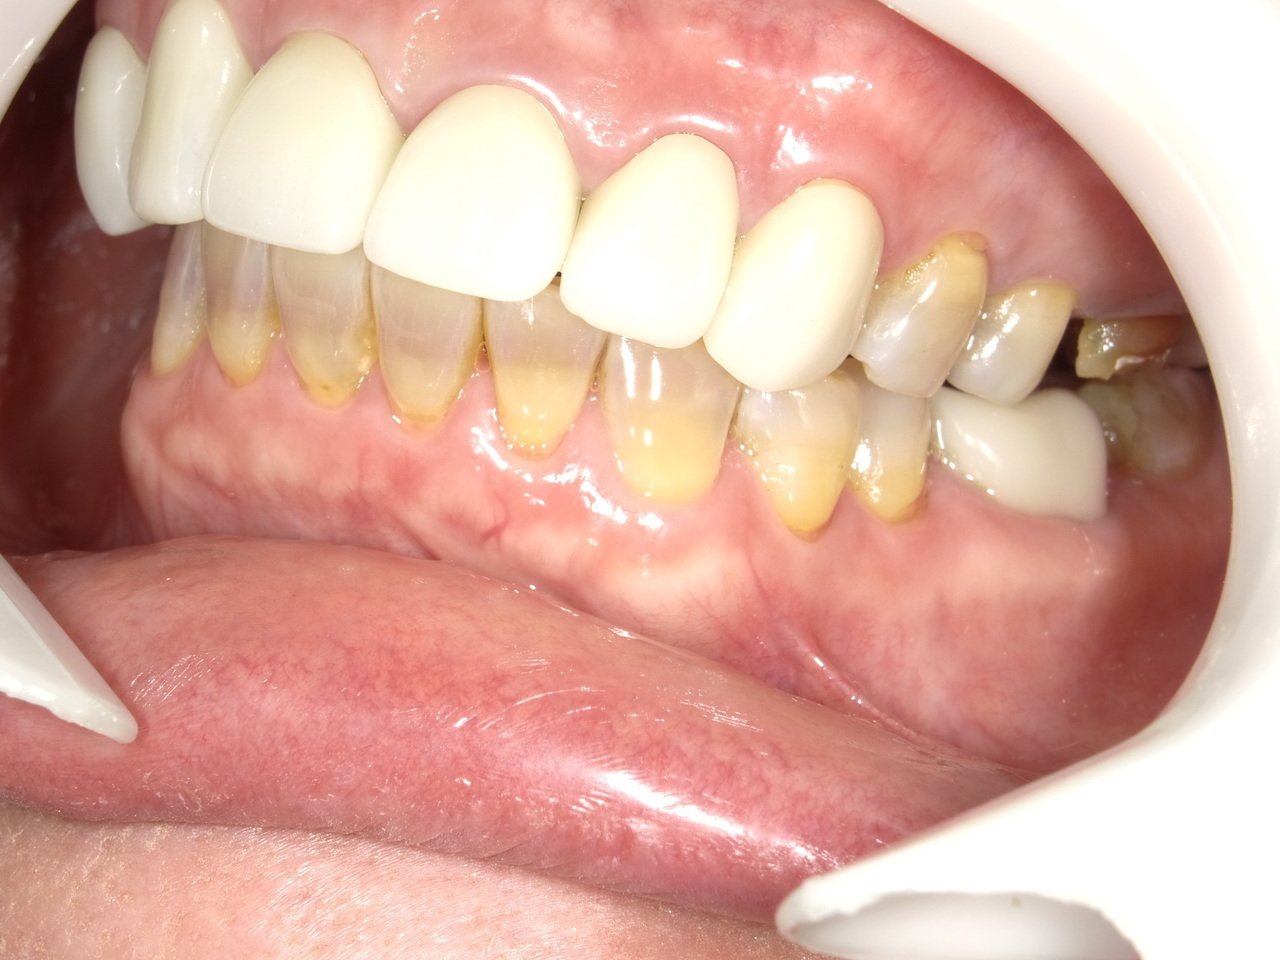

After

枚方市のインプラントの症例

K・S様 女性 60代

症状としては、 右上4から7番までのすべての歯の著しい動揺があり、食事が困難であった。

治療法としては、患者様は、患者様が3か月以内の治療完了を望んでいたために、炎症が若干あったが、右上4から7番ぼすべての抜歯を行い、右上4番(抜歯即時埋入)、右上6番(上顎洞までの骨がほとんどないため、グラフトレスサイナスリフト施行)にインプラントを1回法で手術を終え、2か月半後にインプラントの状態が安定したために、3か月で上部構造の、右上456のジルコニアブリッジを装着して、治療を終えています。

治療結果としては、抜歯したと同時にインプラントを埋入することで、抜歯した穴が自然に治る過程で、インプラントの骨結合と組織の治癒が同時に行われるために、3か月という治療期間で治療を終了することができたことと、機能面・審美面でも回復を行うができた。また、右上6番に関しては、グラフトレスサイナスリフトを行うことで、従来のサイナスリフトに比べ、約9か月早く治療を終えることができました。

治療の期間・回数:約3か月、インプラント抜歯即時埋入から最終補綴物装着まで8回

治療の価格:792000円(税込)

治療費の内訳:インプラント基本料(フィックスチャー(メガジェンインプラントANYONE使用) 及び手術費用、投薬費用、レントゲン費用、インプラント上部費用(アバットメントおよびジルコニアクラウンの費用用)330000円×2 660000円(税込み)。オプション、抜歯即時埋入加算(人工骨費用を含まず)5500円×2 11000円(税込み)右上5ジル9コニアブリッジのポンテック費用 88000円 右上6グラフトレスサイナスリフト費用 33000円(税込み

治療のリスクや副作用:手術後に、痛みや腫れ、出血、合併症などを引き起こす可能性があります。噛む感覚がご自身の歯と異なる場合があります。見た目がご自身の歯と異なる場合があります。手術後にメインテナンスを継続しないと、インプラントが抜け落ちる可能性があります。